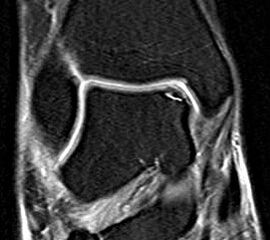

Abbildung 6 und 7, Video 2

Typischer Befund eines fibrotischen Faszikels (*), das zu einem Impingement am rechten lateralen Talus führt. Nach der Resektion des Faszikels ist der Blick auf das anterolaterale Gelenkeck zwischen der Tibia (Ti) und der Fibula (Fi) möglich.

Bei der intraoperativen Palpation mit dem Tasthaken zeigt sich die straffe Spannung des Faszikels und das mechanische Impingement an der lateralen Talusschulter. Oftmals finden sind entzündlich veränderte Synoviaanteile am Faszikel oder auch Schliffspuren am Knorpel der Taluskante.